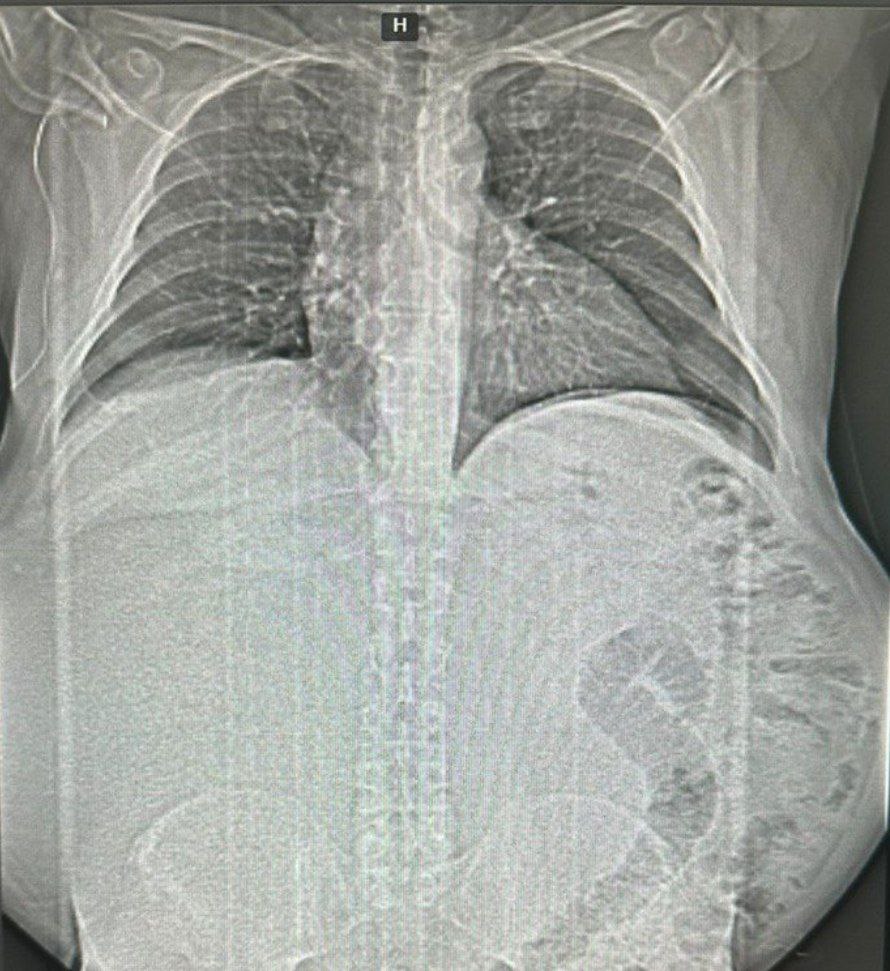

Кубанские медики удалили у мужчины огромную опухоль весом 17 кг

На днях медики хирургического отделения 2 НИИ-КК №1 провели сложную операцию.

К врачам обратился местный житель, который в последнее время стал резко набирать в весе. Однако повышение массы он не связывал с появлением новообразования.

После диагностики удалось выяснить, что в брюшной полости мужчины появилась опухоль.

Медики немедленно назначили операцию, которая продлилась четыре часа. Новообразование удалось успешно удалить. Вес опухоли составил 17 кг.

— Ювелирная работа специалистов не только спасла жизнь человека, но и в очередной раз доказала, как важно вовремя обращаться за помощью к врачам! — написал в своём tg-канале министр здравоохранения Краснодарского края Евгений Филиппов.